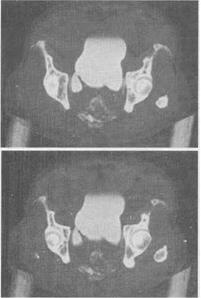

- 单项选择题 男,67岁,排尿困难1年余,加重1个月,结合所示图像最可能的诊断为()。

- A